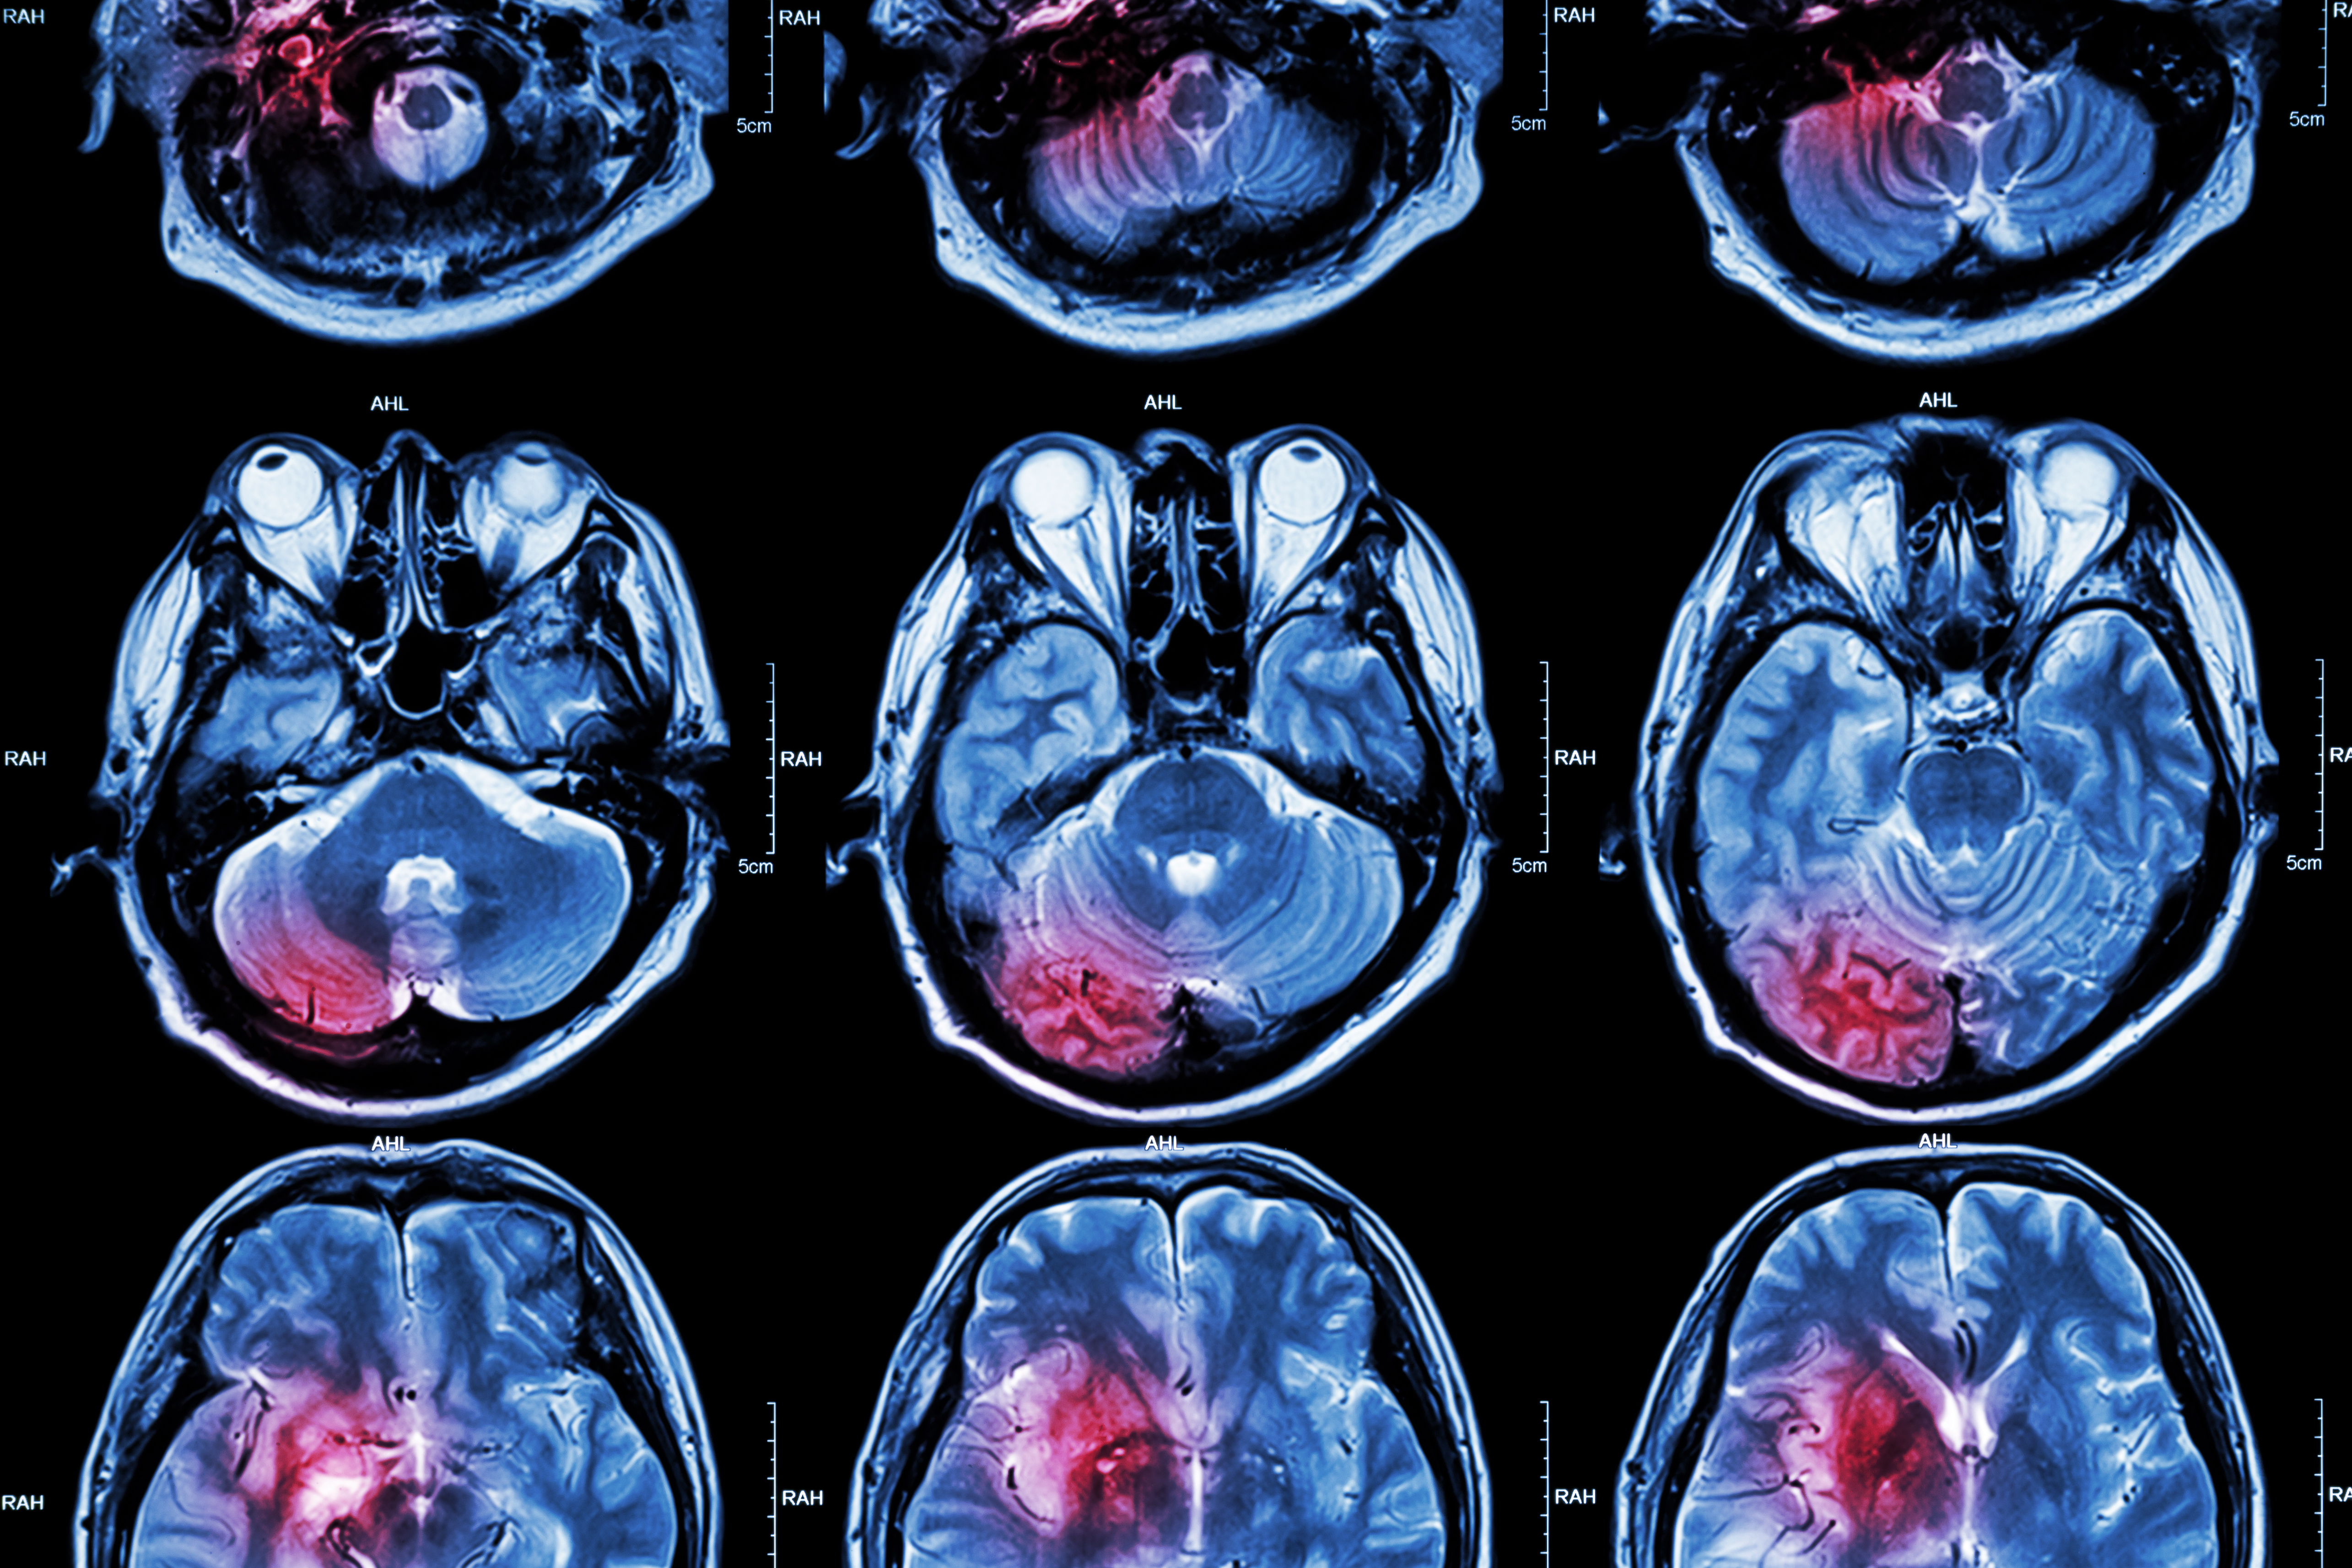

A team of researchers from the University of Cambridge in the U.K. has found evidence on MRI scans that the brain compensates for age-related deterioration by enlisting other areas to help with brain function and maintain cognitive performance.

Previous research has shown that fluid intelligence tasks engage what's called the multiple demand network, which involves regions both at the front and rear of the brain. This network's activity decreases with age. Knights and colleagues investigated whether the brain compensated for this decrease in activity, conducting a study that included MR imaging data from 223 adults between the ages of 19 and 87 who had been recruited via the Cambridge Centre for Ageing and Neuroscience (Cam-CAN).

Image showing bilateral cuneal (magenta) and frontal cortex (brown). Courtesy of eLife/University of Cambridge.

Study participants were asked to identify the "odd-one-out" in a series of puzzles of varying difficulty while lying in a functional magnetic resonance imaging scanner; the researchers measured blood flow to track patterns of brain activity.

Overall, the team found that participants' ability to solve the puzzles decreased with age. But the researchers also reported that in some older people, two areas of the brain showed greater activity and correlated with better performance on the puzzle task: the cuneus, at the rear of the brain, and a region in the frontal cortex.